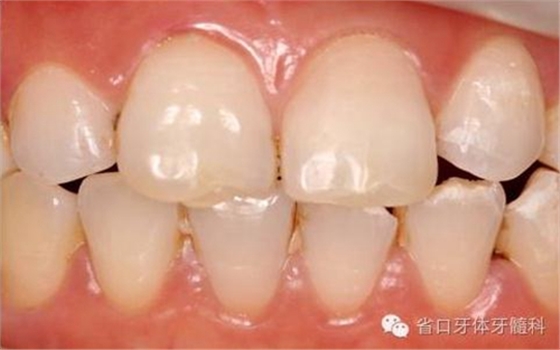

圖2. 術(shù)前口內(nèi)照片,21/冠折。

圖16. 術(shù)后口內(nèi)照

圖18. 術(shù)后23天隨訪的口內(nèi)照片